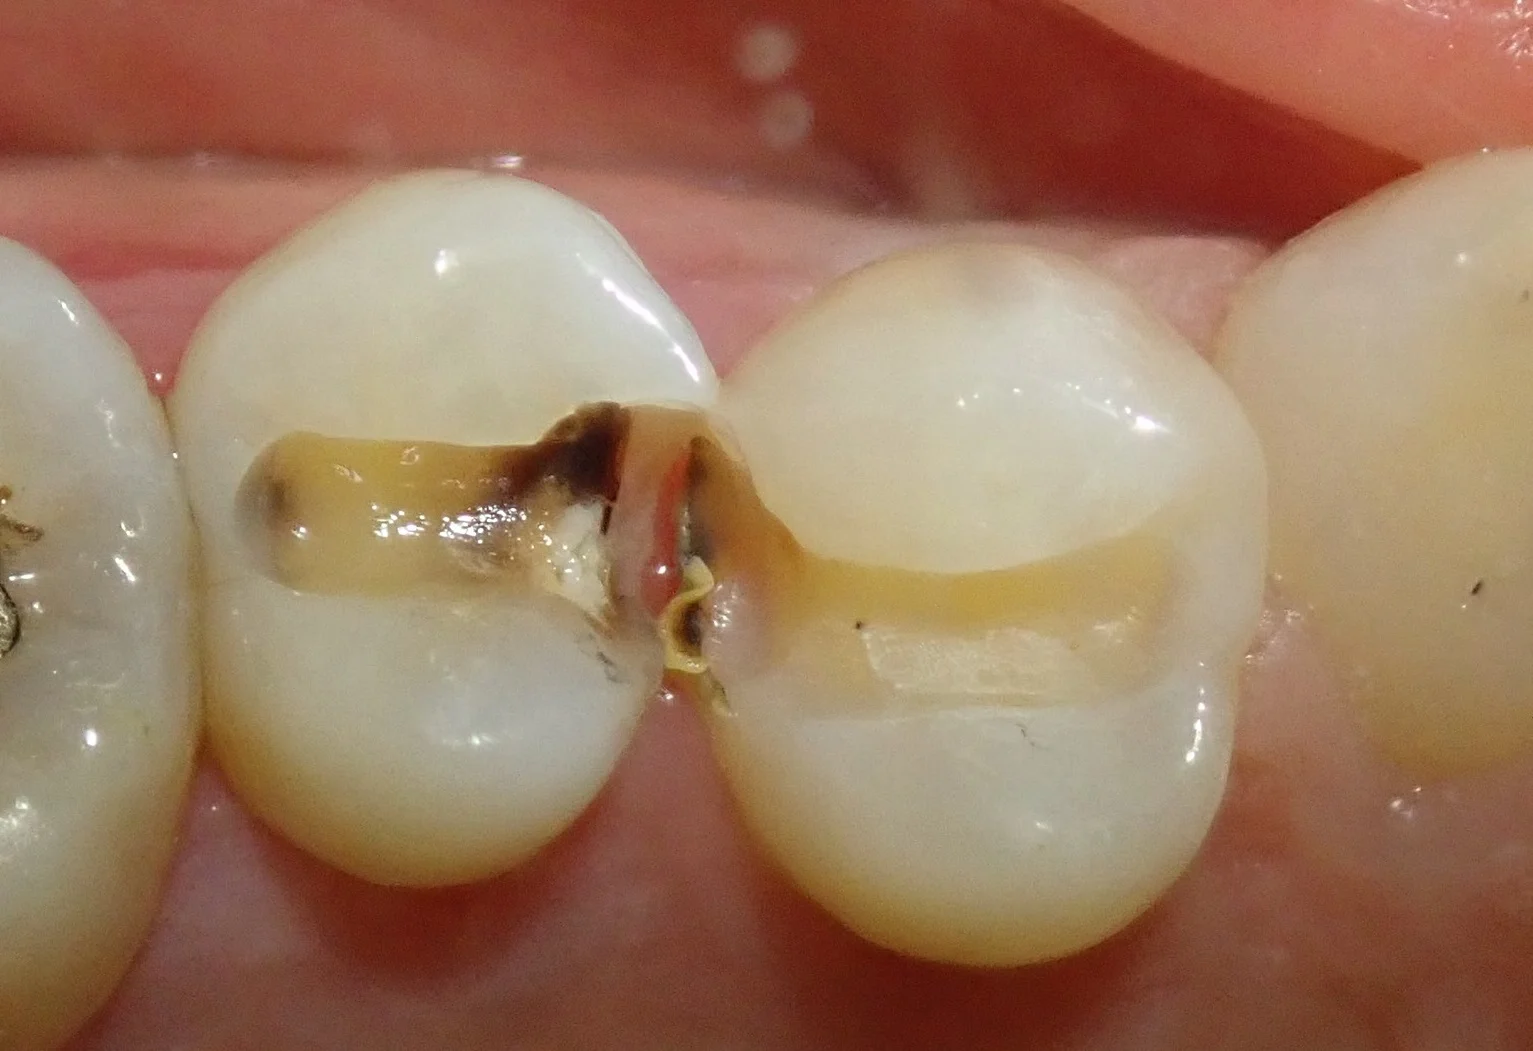

かるーく削ったところ・・・

こんな感じで、中で大きく虫歯が進んでいました。

詰め物だけを除去した写真がこちらです。

右側の歯はそこまでのサイズではなかったですが、やはり左側の歯は歯の中心付近まで見た目上で虫歯になっていました。